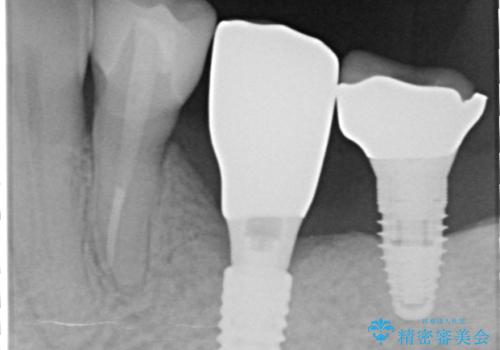

- 単独のインプラント補綴にて咬合の回復を計画した。

インプラントの種類:straumann SLActive

かぶせ物の種類:Bellezza screw retain